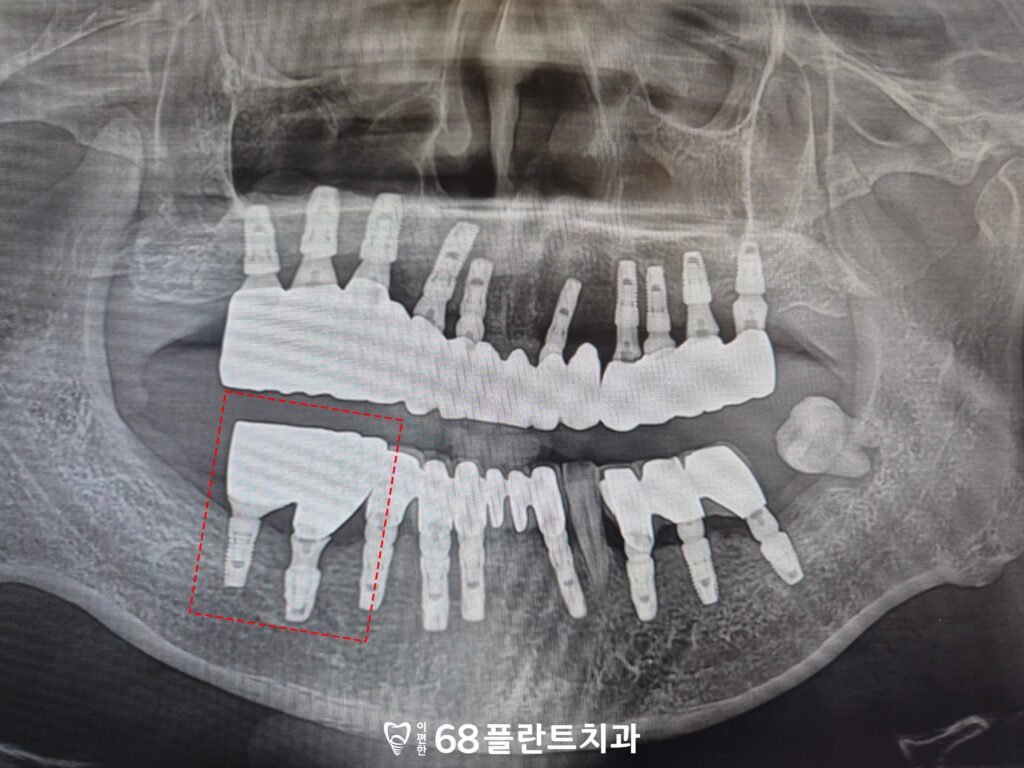

<치조골 소실 심한 상황>

위 환자분께서는

치아가 상실된 부위도 있고

있는 치아들도 흔들리고 불편하다며

본원에 내원해 주셨습니다.

확인해 보니,

오른쪽 위는 치아가 상실된 시간이 길어져

잇몸뼈까지 많이 소실되어 있었으며,

상악동과 거리가 가까워 임플란트를 식립하기에는

골 높이가 충분하지 않은 상태였습니다.

또한 남아 있는 치아들 역시 치주질환으로 인해

지지 조직이 약해져 동요도가 관찰되었고,

전반적인 구강 상태의 개선이

필요한 상황이었습니다.

<타원 임플란트 보철>

또한 오른쪽 아래는

타원에서 임플란트를 식립한 후

보철을 이어서 진행하지 않은 상태로,

임플란트가 기능하지 못한 채 방치되어 있었습니다.

이로 인해 저작 기능이 제대로 이루어지지 않았으며,

주변 치아에도 부담이 가해지고 있는 상황이었습니다.

따라서 해당 부위는 임플란트 상태를 면밀히 평가한 후

보철 치료를 통해 정상적인 기능을 회복할 수 있도록

치료 계획을 함께 수립하였습니다.

<남아있는 사랑니>

마지막으로 전체적으로 사랑니가 남아 있었으며,

왼쪽 아래는 사랑니 앞 치아 부위에

심한 골 소실이 관찰되었습니다.